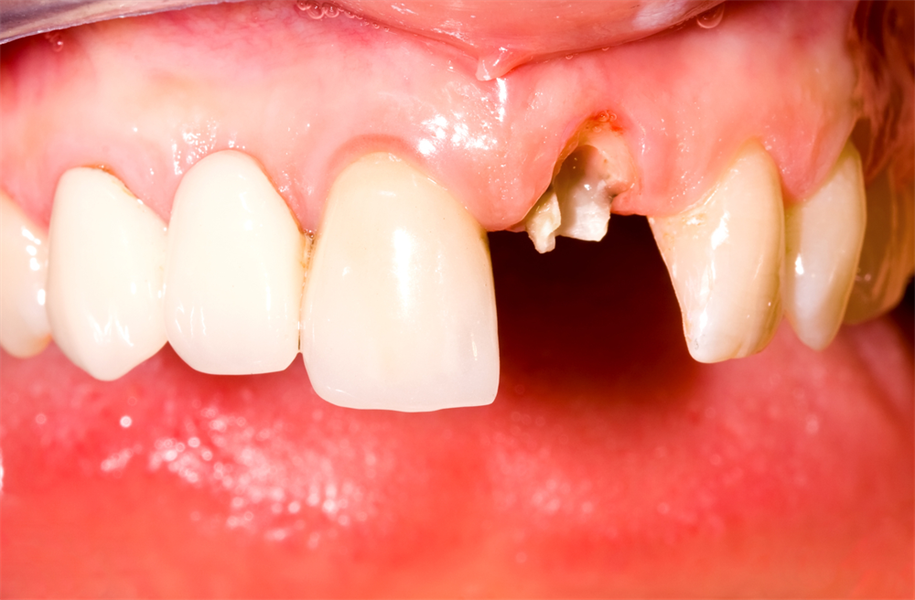

When To Save A Tooth? Part 1: Weighing the Pros and Cons

Implant dentistry has become the standard of care in the 21st Century.  So, when should you remove a tooth and replace it with an implant? This is certainly one of the biggest dilemmas a patient and their dentist can face. As a periodontist who is trained to save teeth, I still believe there is...  Read More